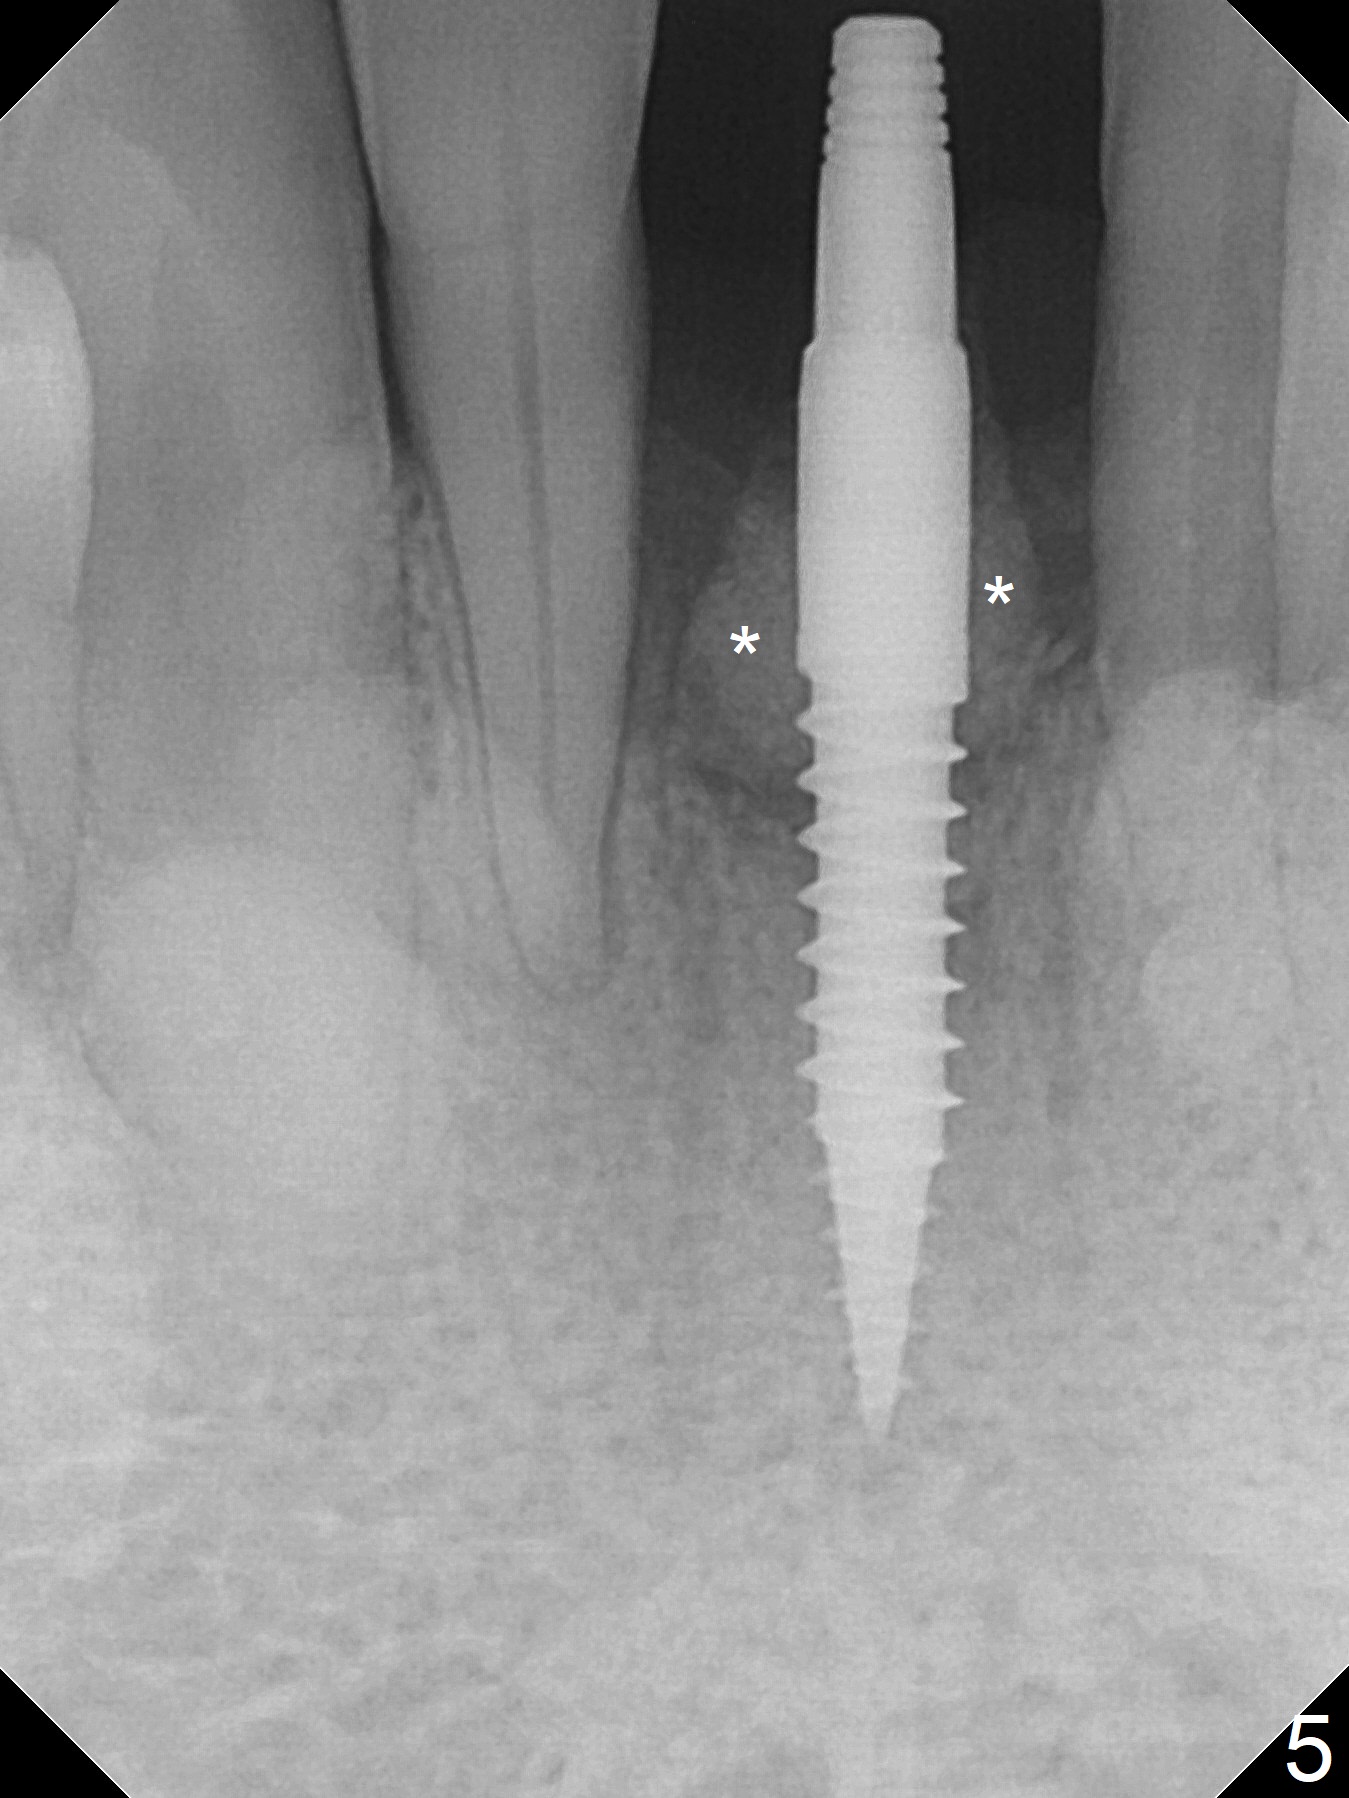

When the patient returns for implant placement 1.5 years after the last treatment (SRP), the tooth #25 has exfoliated, whereas the tooth #24 is severely displaced (Fig.1-3).  In fact the buccolingual plates are found to be lost after extraction, corresponding to change in gingival color indicated by an arrowhead in Fig.1.  Initial osteotomy with 1.2 mm drill is parallel to the terminal branches of the Incisive Canal (Fig.4 arrowheads).  Since the gingiva is as thick as 7.5 mm (Fig.3 arrow), a 3x14 mm 1-piece implant with 4 mm cuff is placed (Fig.5); three implant threads are outside the native bone; with allograft (*) placed and the neighboring crests being coronal to the threads, the chance of periimplantitis should be remote.  An immediate provisional is fabricated to contain the graft in place.  Meanwhile the tooth #2 is symptomatic with crack.  The top 3 threads appear to be contacted by the newly formed crestal bone 6 months postop (Fig.6 *).  Bone appears to have grown into the space between implant threads 6 months post cementation (13 months postop).